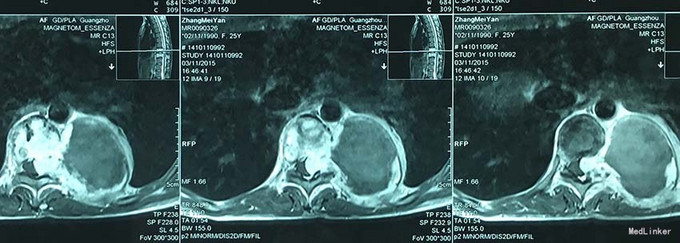

查体:脊柱外观无明显畸形,颈椎活动度正常,胸背部可见纵向长约15cm切口,皮肤钉缝合,伤口愈合可,无红肿渗液。胸椎9-10体左侧棘突旁局部压痛(+)、叩击痛(-),压头试验阴性,双侧侧臂丛牵拉实验(-),双上肢肌张力、运动、感觉及反射无明显异常、躯体感觉无明显减退,双下肢髂腰肌、股四头肌、胫前肌肌力IV级,感觉正常,双下肢直腿抬高试验(-),双侧腱反射对称略活跃,双侧Hoffman征(-),双侧Babinski征(-),双侧髌阵挛(-),踝阵挛(-)。 辅助检查:2015-11外院胸椎MRI检查发现T9-10节段椎体肿瘤并椎旁软组织肿块形成,肿块突入胸腔占位

诊断:胸椎椎体肿瘤(T9-10) 治疗:先于外院行1期后路椎弓根钉固定融合手术,然后转入我院行介入下术前椎体节段血管栓塞手术,第二天行经左侧胸腔入路椎体肿瘤病灶刮除并钛网植骨植入重建手术。术后恢复满意。复查MRI显示肿瘤病灶基本完全切除。